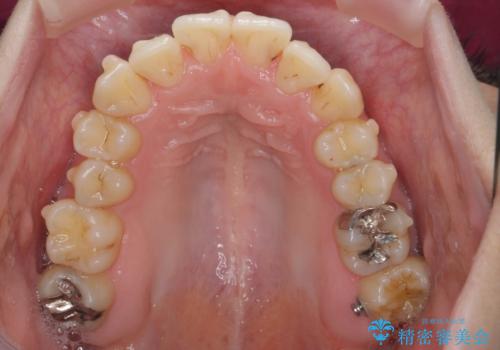

前歯のがたつき すれ違い咬合のマウスピース矯正治療

- 前歯のがたつきや歯の角度、矯正治療を希望され来院されました。

仕事の都合で、ワイヤー矯正を行うことが難しくマウスピース矯正であれば可能、という希望でした。

下顎が前にある咬合関係を可及的に咬合移動で改善し、IPR、下顎3前歯の仕上げで行うマウスピース矯正を計画します。